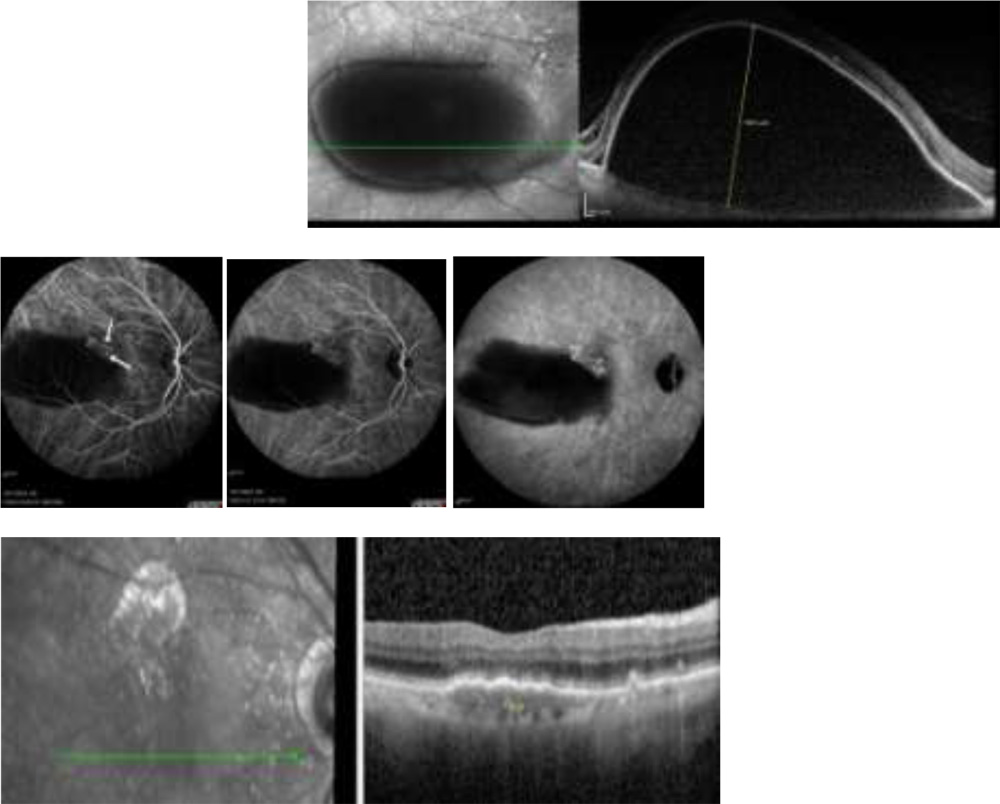

Figure 3 -A case of 64 year female with PED height of 1650 microns and bunch of polyps at notch of PED in ICG showed complete resolution of PED after treatment with focal green laser to a feeder vessel

Figure 3 -A case of 64 year female with PED height of 1650 microns and bunch of polyps at notch of PED in ICG showed complete resolution of PED after treatment with focal green laser to a feeder vessel